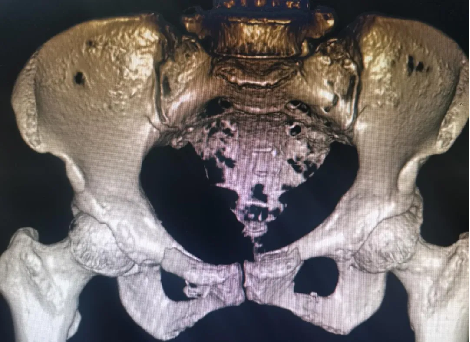

創傷性骨盆骨折致尿道斷裂患者,膀胱(guāng)造瘺術後,需穩定骨折端(duān)避免二次傷害。

骨盆前環微創經皮內固定技術(INFIX技術)固(gù)定結合了內固定和外固定的優點,揚長(zhǎng)避短,針對此類(lèi)患(huàn)者,有效避免了術後深部感染,又避(bì)免(miǎn)了使(shǐ)用外固(gù)定的手術並發症,讓患者在最佳(jiā)治療時機獲得了骨盆環的穩定,並能早期開始功能鍛煉,最大程度上降低了因傷致殘的機(jī)率。